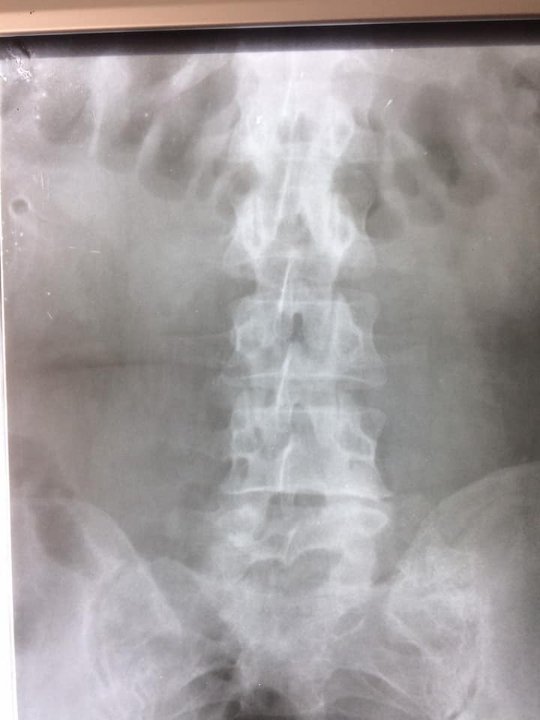

До центру ендоурології Ковельського МТМО звернулася жінка зі сечокам'яною хворобою: камінь миски правої нирки. Про це інформують на сторінці закладу.

Діагноз встановили близько 2-х років тому, проте методи консервативного лікування були неефективними.

Після проведення додаткових обстежень (УЗД та екскреторна урографія) лікарі-урологи провели перкутанну нефролітотрипсію справа. Операція тривала до 45 хвилин.

"Цей клінічний випадок був непростий через наявність супутньої патології у пацієнтки. Вражаючим також був розмір самого каменя 2,5х3,0 см. Проте нашим урологам Миколі Зубку та Мирославі Гаврилюк успішно вдалось видалити камінь повністю та з мінімально можливим травматизмом для пацієнтки. А лікар-анестезіолог Самарчук Т.В. зробила операцію безболісною та комфортною за допомогою епідуральної анестезії", - йдеться в дописі.